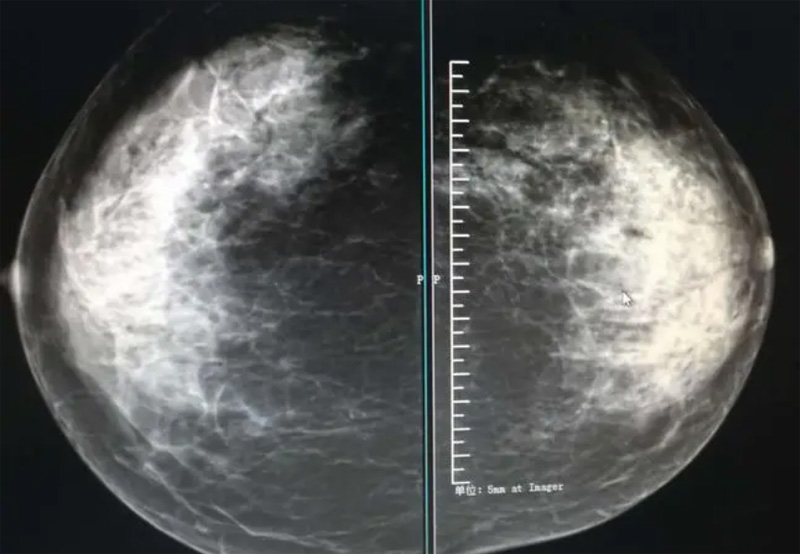

乳腺DR摄影体位有头尾位及内外侧斜位,

乳房在片子的中央,乳头切线位,可见小部分胸大肌,内侧乳腺组织应全部包括在片中,外侧乳腺组织尽可能包括在片中。一张好的MLO位图像显示如下:乳房被推向前上,乳腺实质充分展开,胸大肌可见,较松弛,下缘达到乳头水平,乳头在切线位,部分腹壁包括在片中,但与下部乳腺分开,绝大部分乳腺实质显示在片中。乳腺组织外缘可见乳头的轮廓;乳腺后方的脂肪组织被很好地显示出来,乳房无皱褶。对于CC位及MLO位显示不良或未包全的乳腺实质,可以根据病灶位置的不同选择以下体位:外内侧位(LM)、内外侧位(ML)、内侧头尾轴位(MCC)、外侧头尾轴位(LCC),尾叶位(CLEO)及乳沟位。在临床实践中,对于常规体位上发现的异常改变,可以进一步采取一些特殊的摄影技术,包括局部加压摄影、放大摄影或局部加压放大摄影技术。

2、规范观图程序:屏幕软阅读或在专用日光观片灯下胶片阅读,后者应同时准备白炽强光灯及观片放大镜。注意双侧乳腺配对观察,推荐双眼横向扫描,进行双乳相同部位图像比较分析。